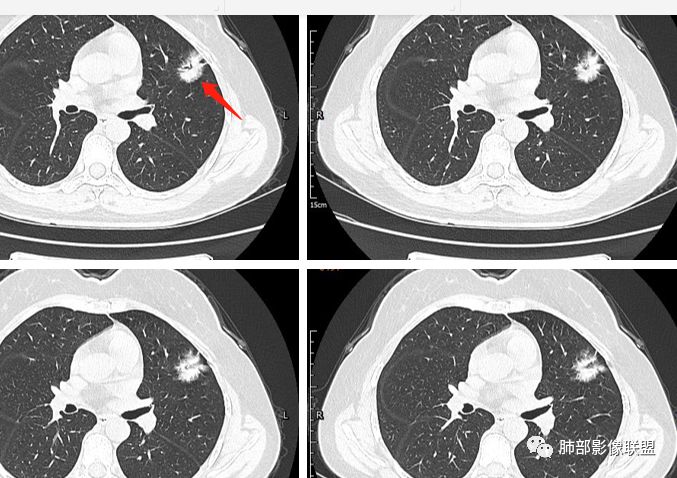

一.大结节影像特点:

左肺上叶胸膜下不规则结节影,分叶、粗短毛刺,胸膜牵拉等,像个“刺头”。

未见钙化,也未显示液化坏死或空洞。

与支气管相关,但取层未能显示支气管进入情况。

有几点应当引起我们高度重视:

1.病灶周围向几个方向膨出的边界清楚的磨玻璃影,这些磨玻璃影时隔几个月依然,几乎可以排除出血及一般的炎性改变。

2.病灶的胸膜牵拉线与其间病灶胸膜侧的磨玻璃边构成朝向胸壁的“月牙铲”结构,这种影像学表现某种程度上反映出病理学特征——病灶收缩+小叶间隔阻挡。

3.病灶实性密度区强化明显,这有助于我们区分一些其他类似病灶,如结核灶等!

4.邻近未见树芽征及卫星灶等。

结合临床,应当高度怀疑浸润性肺腺癌!

二.关于胸膜下小结节:

结节影太小,尚未能够充分反映出影像学特征。随访观察应当是恰当的处置方式。